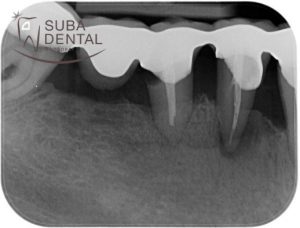

Bone resorption around the teeth, periodontal pockets and inflammation in the intraoral X-ray scans.